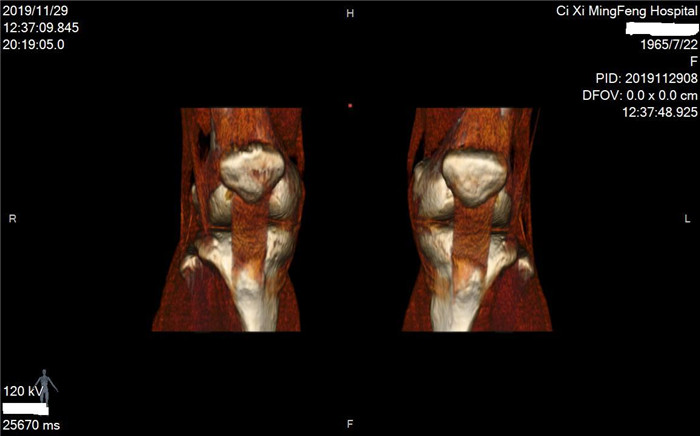

明峰CT搭載了領(lǐng)先的硬件技術(shù)平臺(tái)及系統(tǒng),強(qiáng)大的掃描能力可滿足臨床的各種要求,呈現(xiàn)更極致的細(xì)節(jié),為各臨床科室提供高品質(zhì)的圖像。薄層掃描,消除部分容積效應(yīng),提高各向同性。配合高分辨率算法,有助于細(xì)微結(jié)構(gòu)和形態(tài)學(xué)顯示。